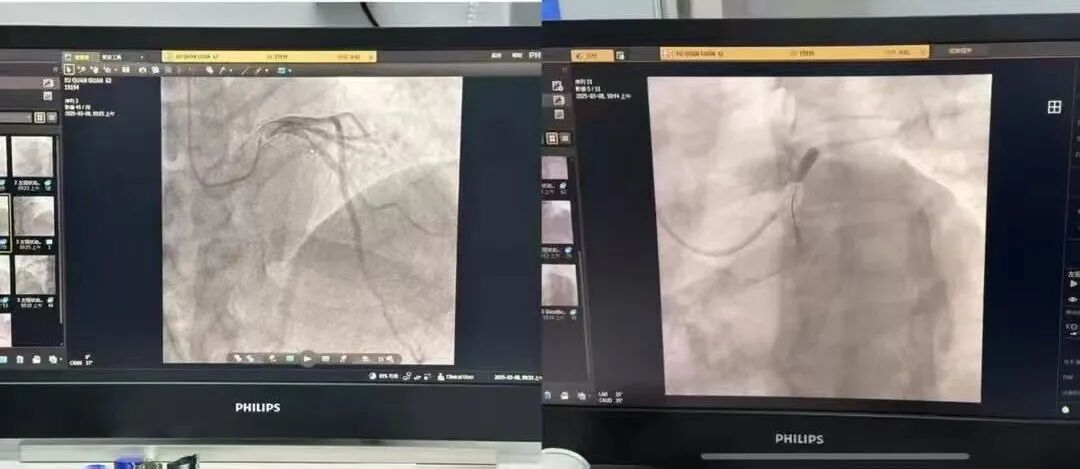

冠状动脉造影+经皮冠状动脉支架植入术

入院后,介入室主任葛兴利在对患者病情全面评估后,与患者家属就病情进行详细沟通。随后,由主任医师葛兴利领衔介入团队为患者实施冠状动脉造影+经皮冠状动脉支架植入术。

在手术过程中,葛兴利主任凭借其精湛技术和丰富临床经验,带领团队紧密协作,导丝通过病变部位,支架定位精准,手术顺利完成。术后患者情况良好,各项生命体征平稳。术后,许先生表示:怀揣信任奔赴而来,满载健康康复而归。

冠状动脉造影+经皮冠脉内支架植入术,是治疗冠心病的重要手段之一,能够有效改善患者心肌供血,缓解心绞痛症状,降低心血管事件的发生风险。该手术通过一条细小的动脉导管进行操作,使用球囊扩张冠脉狭窄的部位,并植入支架以保持血管通畅。